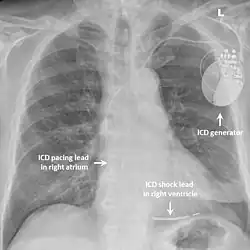

Chest x-ray of a patient with an implantable defibrillator (components labelled)

While medication and sympathectomy aim to prevent abnormal heart rhythms from occurring in the first place, an implantable defibrillator (ICD) may be used to treat arrhythmias that medication has failed to prevent and restore a normal heart rhythm.[2] These devices, usually implanted under the skin at the front of the chest below the shoulder, can continuously monitor the heart for abnormal heart rhythms. If a life-threatening arrhythmia is detected, the device can deliver a small electric shock to terminate the abnormal rhythm and restart the heart.[1]

Implantable defibrillators are often recommended for those with CPVT who have experienced blackouts, ventricular arrhythmias or cardiac arrest despite taking appropriate medication.[2] These devices are life-saving, as it has been shown that their use confers a significant survival benefit in patients with CPVT.[25] It has been suggested that the resulting surge of adrenaline caused by the pain of an electric shock from the device could theoretically bring on a cycle of recurrent arrhythmias and shocks known as an electrical storm,[4] and therefore it is strongly recommended that those with an ICD implanted for CPVT take a beta blocker to dampen the effects of adrenaline.[4]